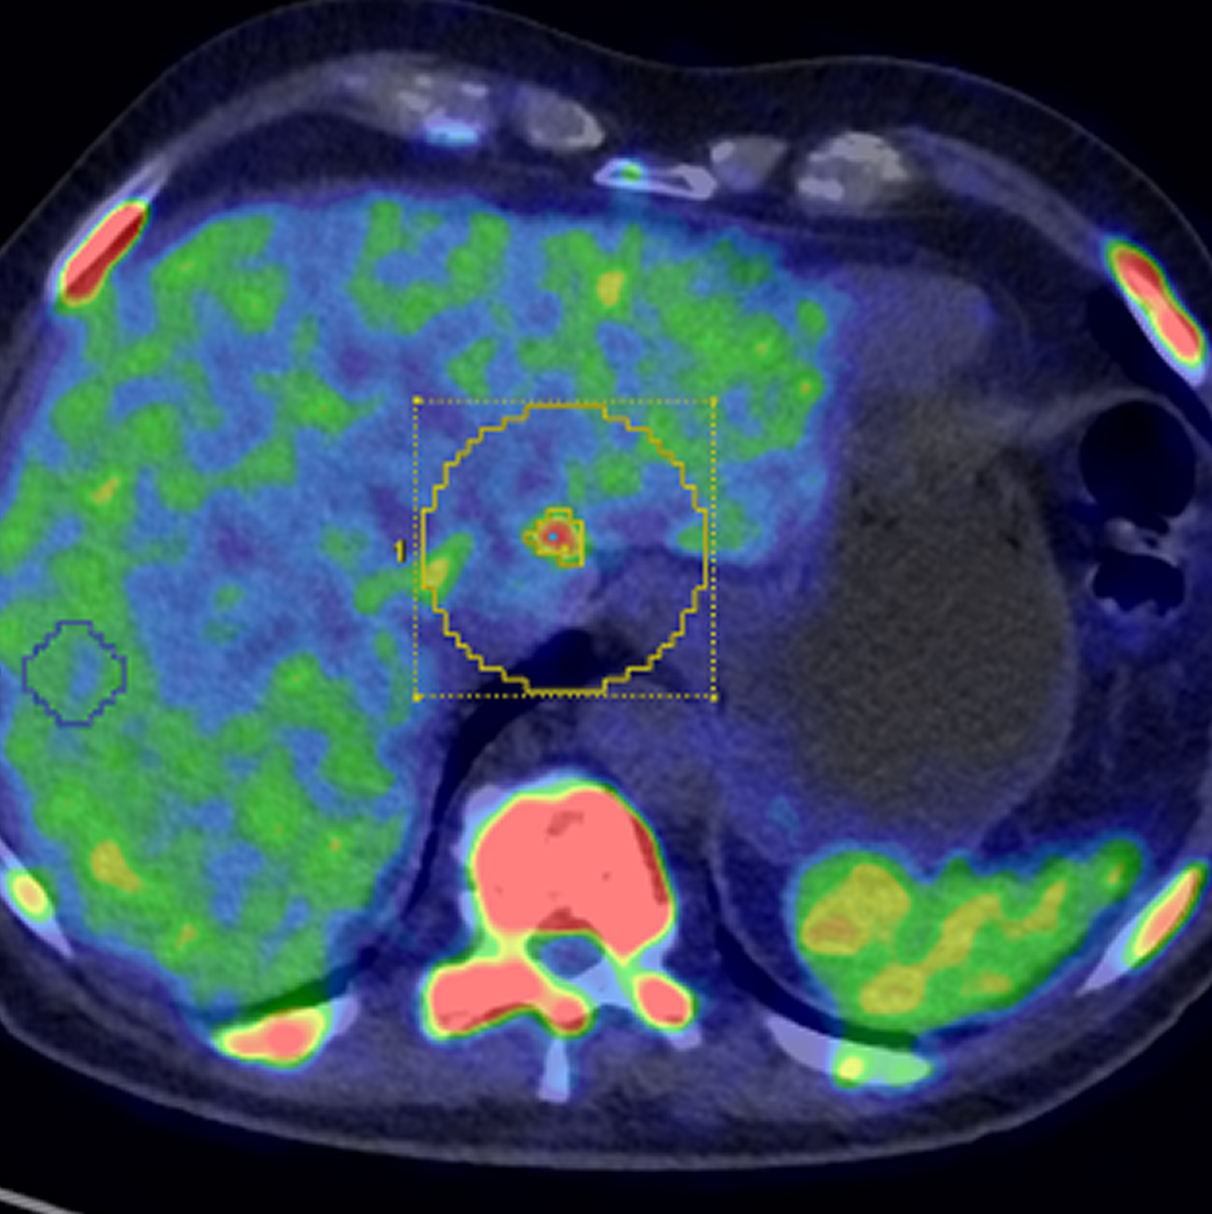

Paziente con anamnesi di malattia coronarica e pregresso impianto di stent sulla discendente anteriore sinistra.

Per prima cosa, esamina l'intera scansione. Concentrati sul tronco comune e sulla porzione prossimale della discendente anteriore sinistra.